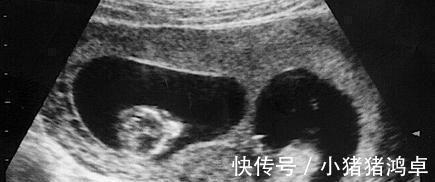

怀胎十月一朝分娩,在很多人的印象中只要到了产房,孩子很快就能出生,不过这也仅限于正常的一个胎儿,但要是两个及以上的胎儿,有可能就会出现分两天出生的情况。

胡女士是一位38岁的高龄孕妈,非常幸运的是,虽然是高龄孕妇,但是怀的却是龙凤胎,这可让全家高兴坏了,一次怀俩,儿女双全这是多少人梦寐以求的事情了。

由于是两个孩子,到了孕晚期的时候全家都做好了要早产的准备,果不其然胎儿在30周的时候就开始发动了,丈夫赶紧带妻子去医院,经过诊断后,胡女士确实是要生了。

医生连忙准备手术,在经历几个小时的分娩,胡女士生下了一个女儿,就在陈女士想要一鼓作气把儿子也生出来的时候,被医生告知子宫硬已经停止收缩,如果继续可能会有危险,需要延期分娩。

胡女士不懂这些专业用语,只能听从医生的,就这样陈女士出了产房,3天后又进入了产房,成功生下儿子,胡女士觉得这次经历非常有意义,就在社交软件上记录了下来,没想到却意外地火了。